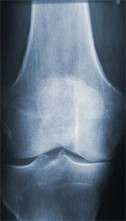

Röntgenaufnahme eines Kniegelenkes mit Arthroseerkrankung

Hier ist der Gelenkspalt auf der Innenseite des Gelenkes aufgebraucht, es ist kein schützender Knorpelbelag mehr vorhanden.